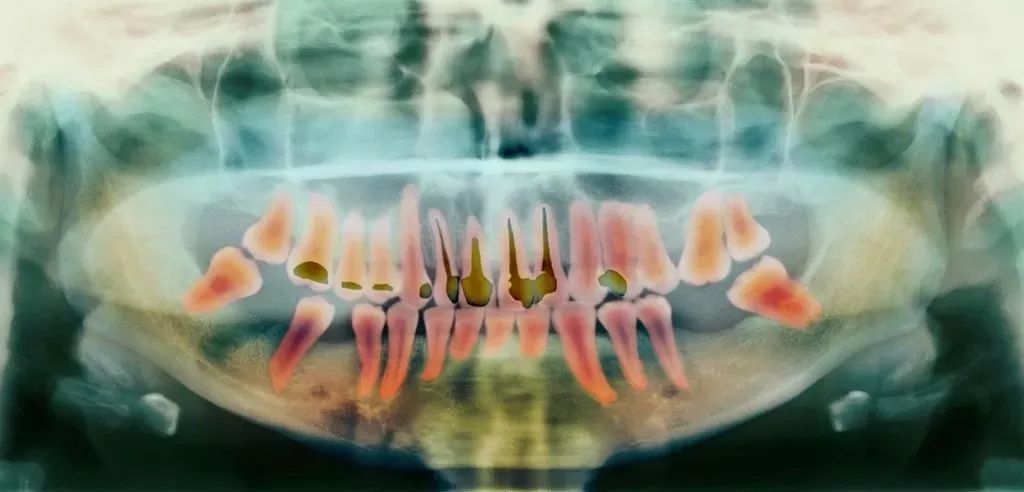

这是目前最有效、最常见的治疗牙髓病和根尖周病的方式,可以消除牙齿内部炎症及其病变源,预防炎症加重扩散,从根本治愈。

一般来说,当你的牙齿遇到下面这些情况:

- 蛀牙坏到牙齿内部,牙髓或细菌感染引起了急/慢性牙髓炎;

- 牙髓由于长期刺激或其它原因造成的死髓牙;

- 意外磕碰、外伤,导致牙根尖血管断裂引起牙神经暴露;

你就需要做根管治疗了。

其过程就是先将牙齿内部坏死的牙髓清理干净,再放入永久性消炎杀菌的药物,最后进行冠修复来拯救这颗牙齿。